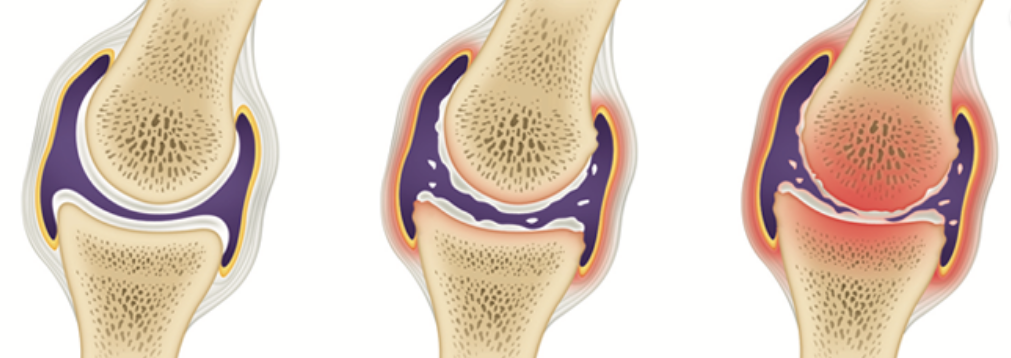

전형적인 관절염의 증상입니다.

관절염을 예방하고, 관절 내 염증을 줄이는 방법에는 적정한 체중을 유지하고, 위에서 말씀드린 근력 운동을 꾸준히 하는 것 외에 관절에 좋은 음식을 섭취하는 것으로도 도움을 받을 수 있어요.

이미 망가진 관절은 되돌리기가 쉽지 않아요. 망가지기 전에 소중한 관절을 관리하고 보호해야겠습니다.

"연골은 지우개와 같아. 한번 닳아 없어진 연골은 다시 생성되지 않아. 미리미리 관리하는게 중요해 "